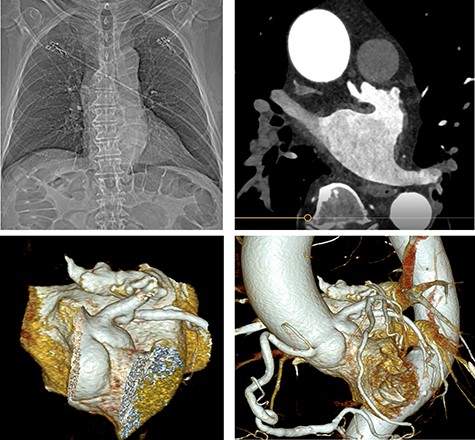

A treatment review for AF was undertaken, but no further action such as MAZE, pulmonary vein isolation, electrophysiology intervention or rhythm control were considered viable strategies. An LAA occluder implantation (Amplatzer Amulet LAA Occluder, Abbott) was carried out under transoesophageal echocardiography (TEE)-guidance and general anaesthesia (Figs 1 and 2). The left atrium was accessed via the right femoral vein (7F 8.5F catheter). The transseptal puncture with an SL1 catheter was pressure-controlled and TEE-guided posterior–inferior, straight to the optimal position. A 6F pigtail catheter was inserted for LAA angiography in right anterior oblique 30°, cranial 20° and caudal 0°.

Cardiac catheterization: LAA occluder implantation; interventional LAA occluder implantation via the right femoral vein and septal puncture under radioscopy and transoesophageal echocardiography (TEE) control.

TEE for interventional LAA occluder implantation; TEE controlled, unsuccessful LAA occluder implantation due to difficult LAA morphology.

The patient’s anatomy showed a large funnel-shaped ostium, with narrow neck and shallow depth and chicken-wing morphology with 90° anterior/frontal angulation. TEE measurements showed a landing zone diameter of ~12–13 mm. A 16 mm occluder was selected. The TorqueVue lock 12F was exchanged via a stiff wire and positioned in the left superior pulmonary vein. No satisfactory position was achieved. For the proximal part, shortly after the ostium with a maximum depth of 12 mm the occluder was too small and exchanged for a 20 mm occluder. This could not be securely positioned; the corpus dislocated in the Timed Up and Go test because of limited contact with the LAA surface. A new transseptal puncture was performed in a more posterior and superior position, the CS catheter removed, and the 7F sheath changed to the SL1. The Amplatzer Amulet 16/20/25 mm LAA occluder implantation remained challenging due to the unusual anatomy with an atypical position of the auricular appendage. Finally the procedure was aborted in favour of a LAA clip.